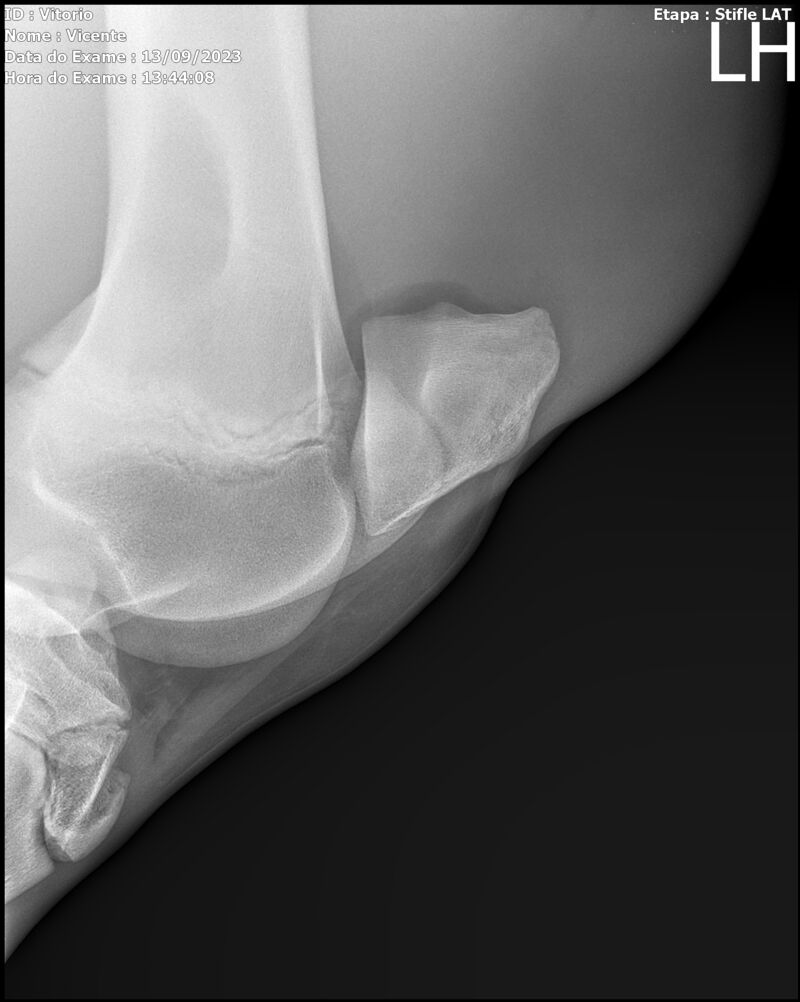

LOTE 13

THUNDER ZC

Raça: BRASILEIRO DE HIPISMO

Sexo: MACHO - POTRO

Nascimento: 17/09/2022

Altura Aproximada: 1,54

Pel.: CASTANHO

Registro: EM AND

Vend.: VICENTE CONTE

Local : PORTO FELIZ/SP